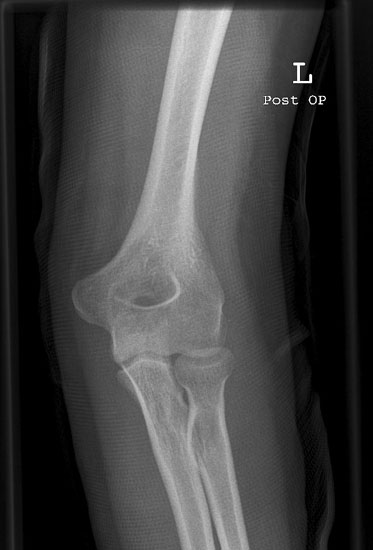

Ellenbogen seitlich

Fehler

Der distale Oberarmteil ist schräg projiziert, d.h. die beiden Gelenkrollen überdecken sich nicht. Hier gibt es eine Doppelkontur der Gelenkrollen in Richtung Handgelenk hin. Ursache hier ist die Schrägprojektion, da Unterarm nicht unterpolstert wurde.

Abhilfe

15°-Keil oder Handgelenk der Gegenhand unter den betroffene Unterarm/Handgelenk legen.